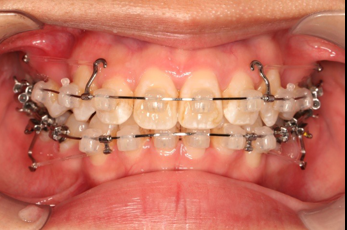

2018.11.14  术后磨牙尖牙I类关系,中线齐,覆合,覆盖正常

Post-TXPRE-TXPost-TXNormFMIA°47°57.555.0SNA°77.7°76.883.0SNB°70.2°73.780.0ANB°7.5°3.13.0FMA° 29.828.026PFH/AFH70.5°65.970Z Angle°50.3°64.477U1-FH113.0103.7110.0 IMPA°103.291.197.0U Lip tos’ line6.3 mm3.25.0L Lip to s’ line3.9 mm1.03.0OP-FH1212.615

宏观评价:面部对称,面下三分一比例协调,上下唇凸度正常,上颌牙列内收转矩控制良好,下颌后缩改善,颏唇沟变得更加柔和,术后达到基本直面型。

迷你观评价:上下牙齿中线与面中线对齐,笑弧协调,微笑时牙龈暴露量正常,微笑时横向正常,左右唇基本对称。

微观评价:牙齿整齐,咬合关系良好,上下前牙转矩及突度控制良好,磨牙关系I类,尖窝咬合关系良好,OB,OJ正常。